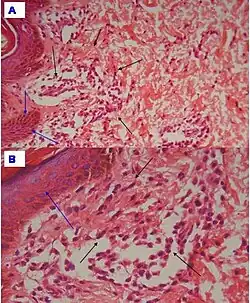

| Urticaria, lymphocyte predominant | Perivascular location. Mast cells are relatively sparse, potentially demonstrated with special stains, preferably tryptase stain. Extravasated erythrocytes are present in about 50% of the cases. No vasculitis.[14] | Dermal edema [solid arrows in (A,B)] and a sparse superficial predominantly perivascular and interstitial infiltrate of lymphocytes and eosinophils without signs of vasculitis (dashed arrow).[15]

| Urticaria, lymphocyte predominant | Perivascular location. Mast cells are relatively sparse, potentially demonstrated with special stains, preferably tryptase stain. Extravasated erythrocytes are present in about 50% of the cases. No vasculitis.[14] | Dermal edema (solid arrows) and a sparse superficial predominantly perivascular and interstitial infiltrate of lymphocytes and eosinophils (dashed arrow)

| Prevesicular stage of bullous pemphigoid | Image at right shows influx of inflammatory cells including eosinophils and neutrophils in the dermis (solid arrow) and blister cavity (dashed arrows), and deposition of fibrin (asterisks).[15] However, the diagnosis of bullous pemphigoid consist of at least 2 positive results out of 3 criteria:[19]

|